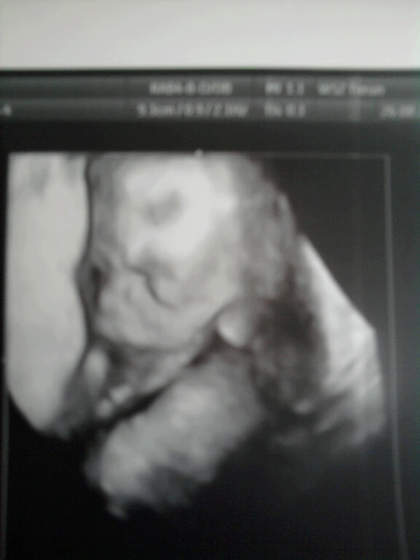

Moja śłiczna mała synowa :-)

... mam nadzieję że twoja mała synowa nie wyskoczy z brzucha z siusiakiem![]()